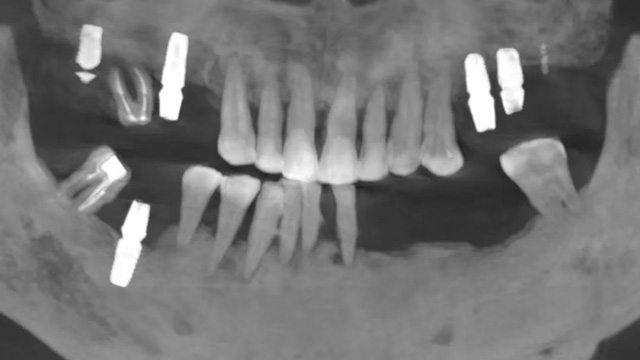

据新桥口腔成都蜀汉院区种植专科主任姜辰介绍,张先生的口腔情况较为复杂:之前种植的6颗种植牙牙冠全部脱落,只剩下种植体,其中一颗种植体已折断,还有两颗牙做过根管治疗,其中一颗牙冠脱落,此外,他口腔里还存在多颗牙齿缺失和松动等问题。

张先生10年前种下的6颗种植牙牙冠全部脱落

经过询问,医护人员得知张先生当年种完牙后,还没等到佩戴正式牙冠就离开成都了,他花“巨资”种下的6颗牙这么多年来只有临时牙冠。“临时牙冠是作为过渡使用的材料,在硬度、咬合、稳定性等方面都比不上正式的牙冠,影响到了种植牙的正常使用寿命。”牙冠脱落后,张先生继续使用仅剩下“光杆”的种植体进行咀嚼,最终导致种植体受损,发生折断、松动等情况。